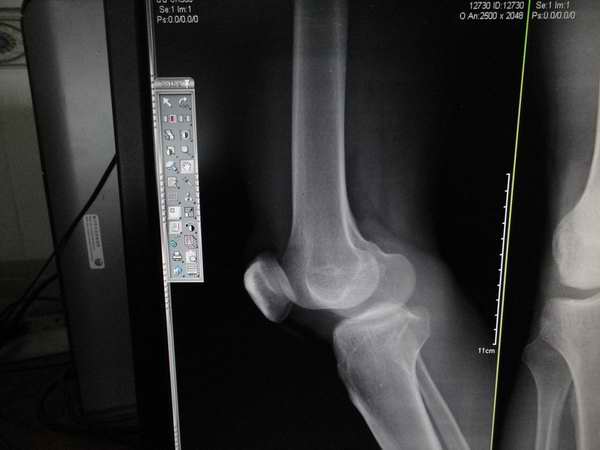

标题: X7107:看法,外伤,患者膝关节间隙内窄外宽改变,你们会不 [打印本页]

标题: X7107:看法,外伤,患者膝关节间隙内窄外宽改变,你们会不

1、外伤患者,可以提示半月板损伤,也可以写结合临床。

第一例:建议行mri检查。

提示“膝关节间隙内窄外宽改变,请结合临床或进一步检查”。看不见半月板,普放不能报。

第一个病例报告时要提示膝关节间隙馁窄外宽改变,建议结合临床或进一步检查,第二个病例支持考虑胫骨平台骨折后改变。

“膝关节间隙内窄外宽”如果没有外伤病史的话,也可以是膝关节退行性骨性关节病的表现,有没有半月板损伤平片没有权力诊断,有外伤史可以结合临床看外侧副韧带有没有损伤,拍双膝夹枕位片可有助于诊断